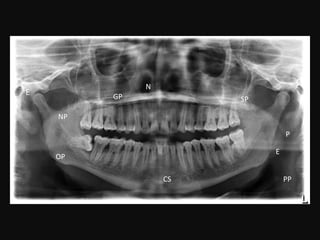

N

SP

P

PP

NP

E

OP

GP

CS